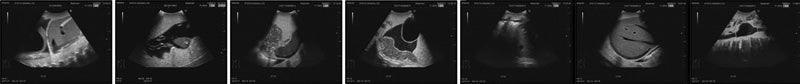

Dieses Übungsmodell wurde entwickelt um die FAST (Focused Assessment with Sonography for Trauma) Untersuchung zu üben. Diese Untersuchung dient dazu, freie Flüssigkeiten im Intraperitonealraum oder Perikard zu ermitteln. Die Übungsmöglichkeiten umfassen folgende Untersuchungen: FAST-Prozeduren: Innere Blutungen im Bereich der Leber, der Niere, im Becken und im Perikard Sonografie von Notfallpatienten: Innere Blutungen im Bereich des Perikard, der Pleurahöhle, der Leber, der Milz und der Blase, Pathologien wie Gallenblasenentzündung, ein Aneurysma der Aorta und eine Verletzung des Darms. Die Abbildungen zeigen folgende Ultraschallbilder: 1. Herztamponade 2. Blutung im rechten oberen Abdomen 3. Blutung im linken oberen Abdomen 4. Blutung im Becken 5. Pleuraerguss 6. Perihepatische Blutung 7. Aortenaneurysma Das Modell wird geliefert mit einem Transportkoffer und einem Lehrvideo auf DVD. Größe: 61 x 30 x 30 cm, Gewicht: etwa 31 kg - Lieferzeit ca. 14 - 21 Werktage